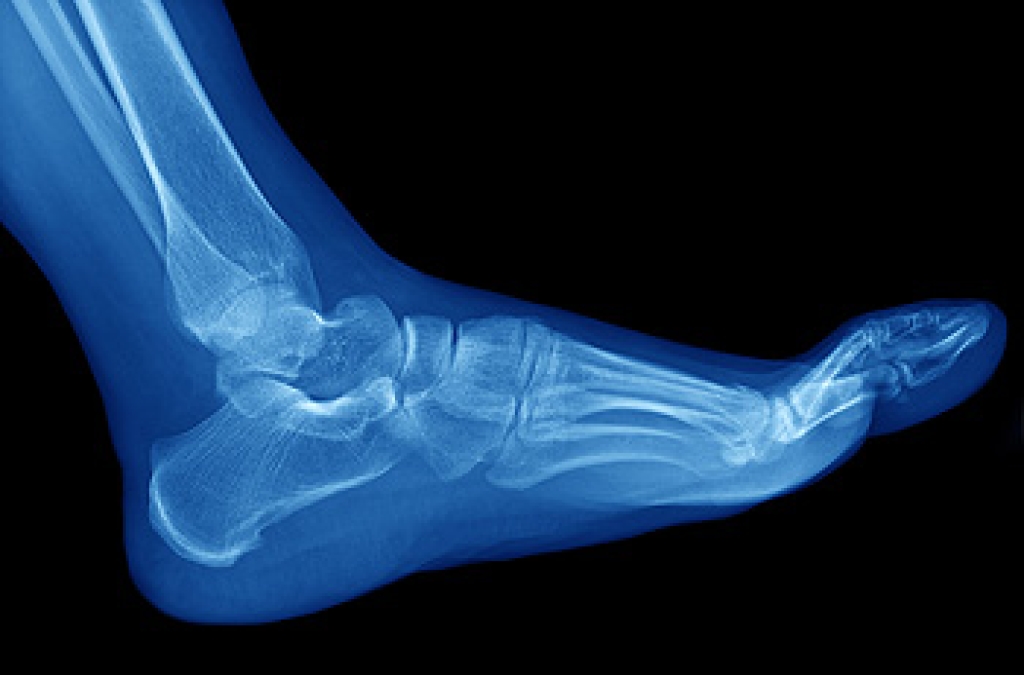

Podiatrists are medical professionals who diagnose, treat, and offer preventative care for problems that affect the feet, ankles, and lower legs. Podiatrists may treat various foot and ankle injuries, such as plantar fasciitis, ankle sprains, and stress fractures. They can also address foot deformities, such as bunions, and skin or nail conditions like athlete’s foot or fungal toenails. A podiatrist might play a major role in a patient’s care if they have diabetes, poor circulation, or neuropathy, as these conditions frequently affect the feet. Some podiatrists are also trained in surgery. If you have developed a foot or ankle problem, it is suggested that you consult with a podiatrist.

Stress fractures in the feet are a common injury, particularly among athletes. They can be caused by any activity that puts increased pressure on the feet, from playing a high impact sport to starting a new workout routine. A sudden increase in activity, for example, running for much longer than usual, can overload the bones in your feet. Changing the surface that you train on can have a similar effect, specifically if you are moving from a soft surface, like turf, to a hard one like asphalt. Having an improper running technique or wearing the wrong shoes can also lead to stress fractures. If you are suffering from any type of foot pain, please seek the care of a podiatrist.

Stress fractures occur in the foot and ankle when muscles in these areas weaken from too much or too little use. The feet and ankles then lose support when walking or running from the impact of the ground. Since there is no protection, the bones receive the full impact of each step. Stress on the feet can cause cracks to form in the bones, thus creating stress fractures.